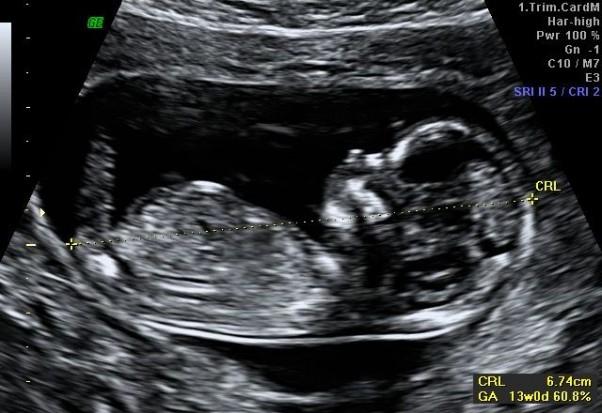

byliśmy rano na wizycie :D pan doktor zbadał zmierzył Cię i wygląda na to że jest wszystko w jak najlepszym porządku :D ma już ponad 6 cm długości serduszko mocne i rytmicznie bijące ale kim jest nie wiemy jeszcze na 100% choć skłania się w stronę kolejnej dziewczynki :D moje wyniki są wręcz książkowe waga tylko spadła o kio ale to pewnie z powodu wymiotów :( teraz już będę jeść więcej bo czuję się lepiej :D